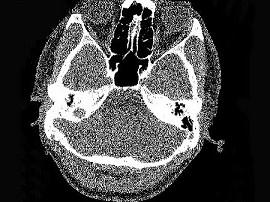

男,23岁,右耳流脓十余年,右外耳道流脓,鼓膜穿孔,CT检查如图,最可能诊断为 ( )

• A.中耳癌

• B.嗜酸性肉芽肿

• C.(海绵化期)耳硬化症

• D.中耳乳突结核

• E.慢性中耳乳突炎

答案: E